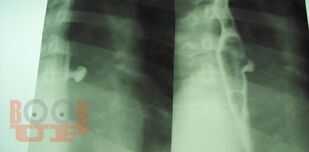

Рентгенодиагностика дивертикулов пищевода, желудка и двенадцатиперстной кишки

В методическом пособии на основании многолетнего личного опыта автора и литературных данных изложены основные сведения о диагностике дивертикулов пищевода, желудка и двенадцатиперстной кишки.